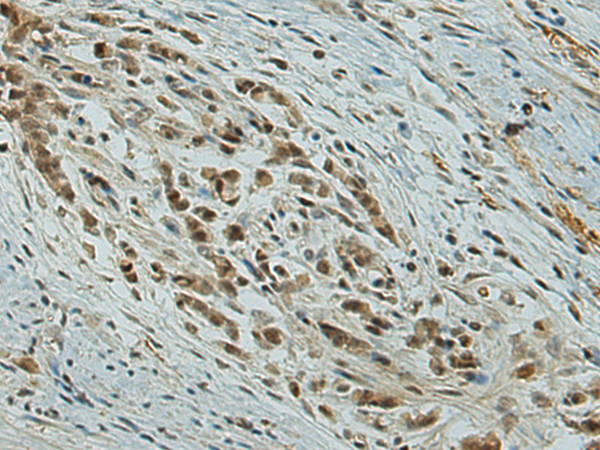

分类: 科研抗体货号: P12491别名: BARS应用: WB,IHC反应种属: Human, Mouse, Rat